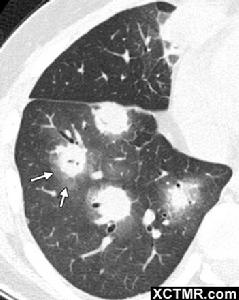

牛眼征是指肝臟繼發性腫瘤影像學檢查時可見的影像學表現。B超:肝內單發或多髮結節,可為低回聲、強回聲或不均勻回聲,腫塊內部回聲為高回聲,周圍包繞寬0.5~...